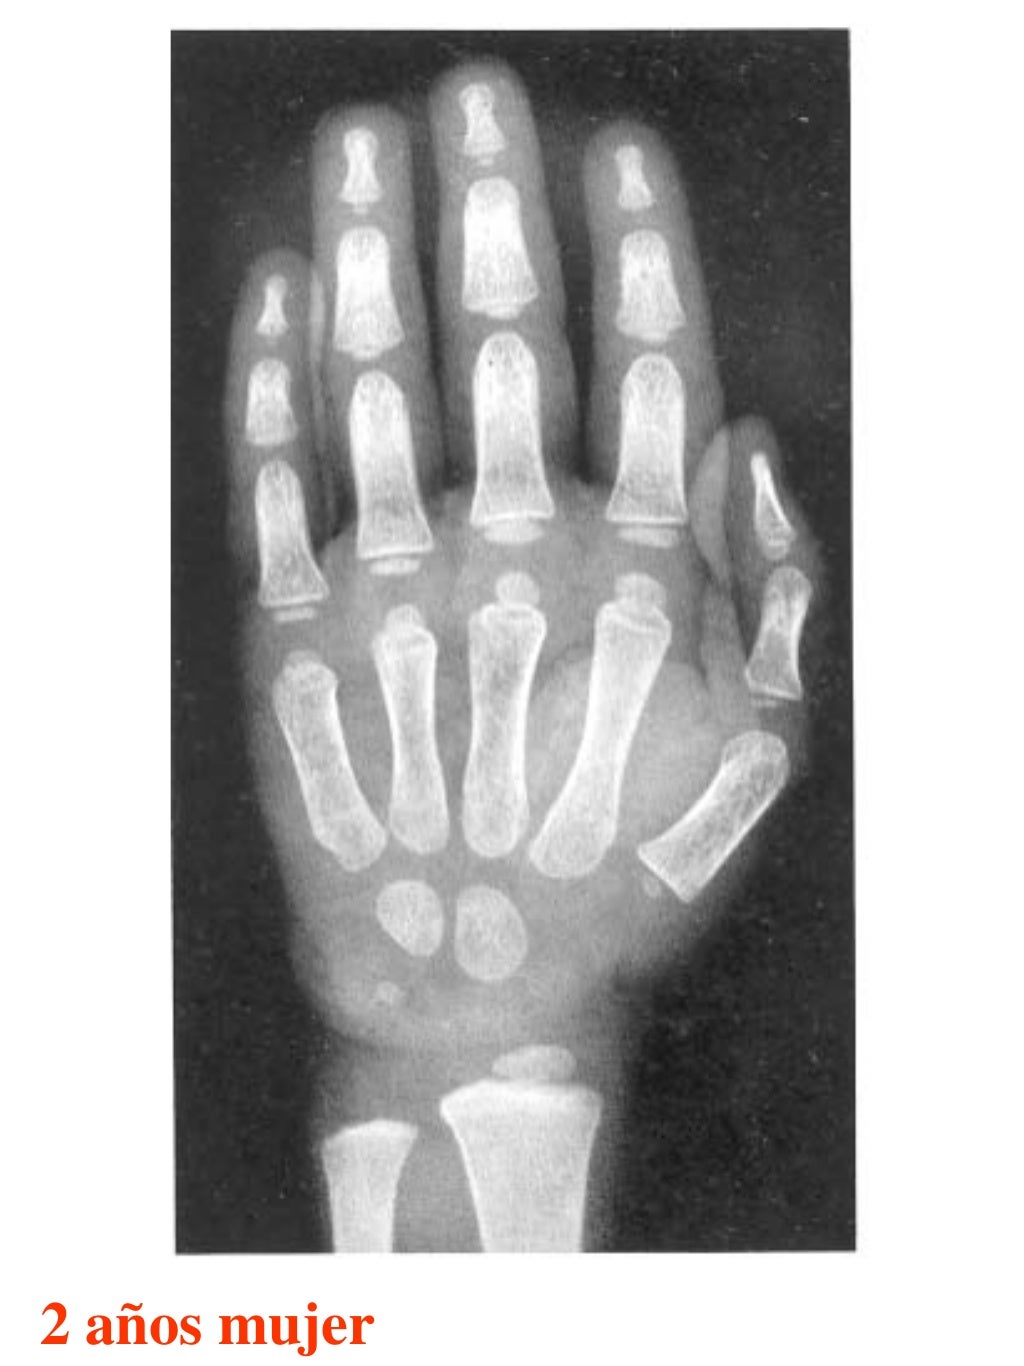

Tablas De Greulich Y Pyle . Scribd is the world's largest social reading and publishing site. This systematic review summarizes the. The radiographic atlas of skeletal development of the hand and wrist by ww greulich and si pyle is a classic radiological. The standards established by greulich and pyle, undoubtedly the most popular method, consist of two series of standard plates. The greulich and pyle method is one of the two main ways to assess the bone age of children. El documento lista las edades. Both main methods of bone age. 153 recomendaciones • 616,869 vistas. Atlas greulich y pyle | pdf | descarga gratuita. The greulich and pyle atlas is used to estimate the age of children and adolescents.

Tablas De Greulich Y Pyle The standards established by greulich and pyle, undoubtedly the most popular method, consist of two series of standard plates. The standards established by greulich and pyle, undoubtedly the most popular method, consist of two series of standard plates. El documento lista las edades. This systematic review summarizes the. The greulich and pyle method is one of the two main ways to assess the bone age of children. Both main methods of bone age. Scribd is the world's largest social reading and publishing site. 153 recomendaciones • 616,869 vistas. Atlas greulich y pyle | pdf | descarga gratuita. The greulich and pyle atlas is used to estimate the age of children and adolescents. The radiographic atlas of skeletal development of the hand and wrist by ww greulich and si pyle is a classic radiological.